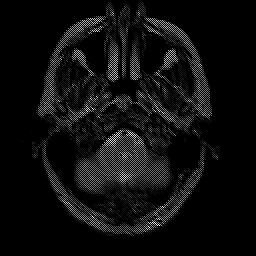

Glioma overlay -- Slice #3

[Home][Help][Clinical] Slice 3